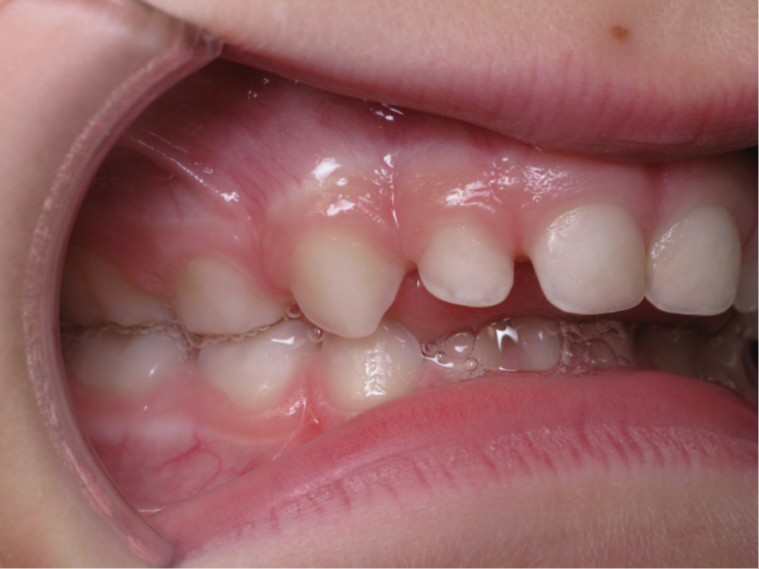

6 décalage sagittal 5 ans

Décalage entre les dents d avant en arrière

surveillance évolution de la dentition pendant 4 ans